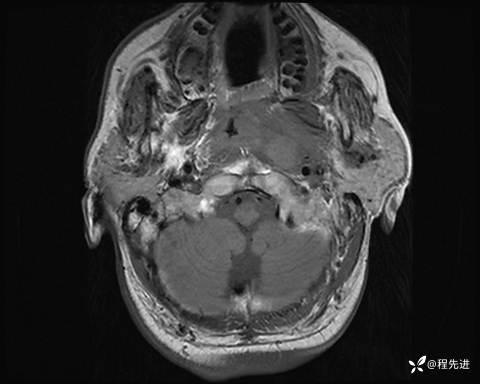

MRI平扫+增强:

T1: